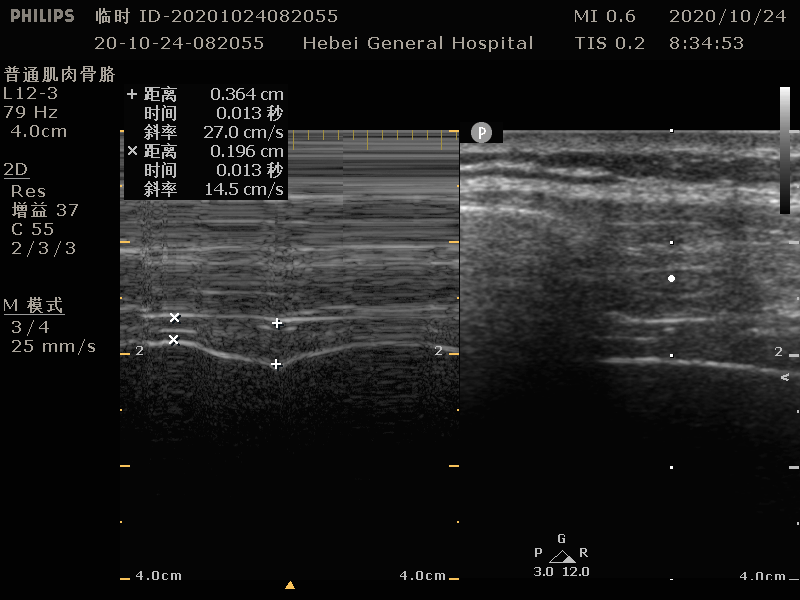

切换 M 模式,观察 3 个平静呼吸周期,并测量周期内最高点(吸气末)至最低点(呼气末)的位移(图 3 )。

图 3 M 模式-膈肌移动度的测量(注:红色箭头所指的垂直测量,是膈肌位移)

平静呼吸时为 1~3cm ,用力深吸气可达 7cm 左右。低于 1cm 时可提示膈肌功能障碍。